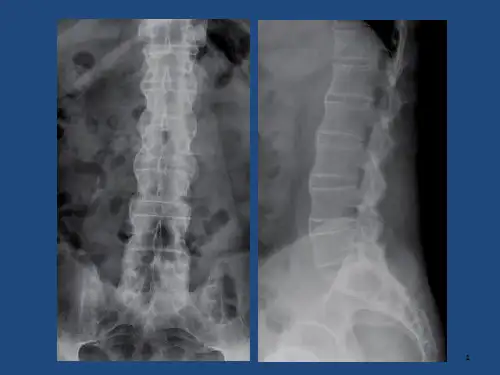

强直性脊柱炎(Ankylosing Spondylitis,AS)是一种慢性、进行性的关节炎,

主要累及脊椎及骨盆关节,常表现为脊柱强直及关节疼痛。